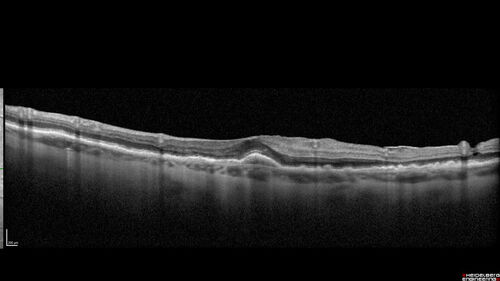

Fresh BRAO in patient with wet AMD

91 year old female She noticed last night a shadow over the left eye. When she closes her right eye she cannot see the bottom of the vision in the left eye. This is new.

VA OD: sc20/32-1

VA OS: sc20/32-2

BRAO in patient under treatment for wet AMD